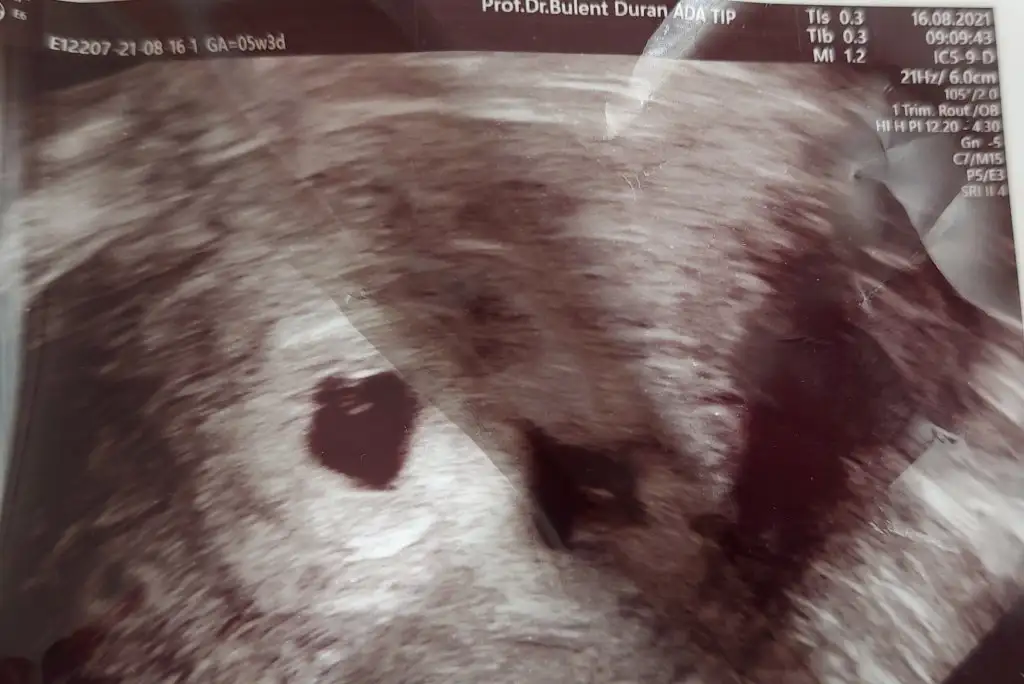

Ilk sefer benim de kucuktu, bu kez buyuktu ama olcmemis herhalde; ekliyorum usg'yi:Benim perşembe sabah daha da netleşecek inşallah öyle demişti doktorum ilk gittiğimde çok ufaktı keselersenin bugün yolk göründüğünde kese boyutların ne kadardı canım?

Ölçmemiş ama çok güzeller yaIlk sefer benim de kucuktu, bu kez buyuktu ama olcmemis herhalde; ekliyorum usg'yi:

Vajinal bakiyor canim... yav demingene kanama oldu fitille durdurduk, 12. Haftaya kadar boyle hep kalp krizi mi gecirecegim!! Burada benim hala var korkmayin diyenler olmasa kendimi salardim, sayenizde sakince atlatmaya calisiyorum her atagi, insallah bebekler saglamdir ve dayaniriz hep beraber..Son bir soru dahavajinal mi baktı abdominal mi

Canim benim bebeğin gelisimi durdu 8 haftalikken utrasonda 5 haftalik görünüyordu 2 haftada kese gelişmedi cuma günü kürtaj oldumKızlarrr napıyosunuzzz kaç haftadır giremedim buraya özledim sizlerii nasıl gidiyorr herkesin herşeyi yolunda mııX xnobodyx nilnec @Saturnyildizi A Alyamalis remziye_06 @Hayalim11 B Bebegmgelecek @Nisanesintisi01